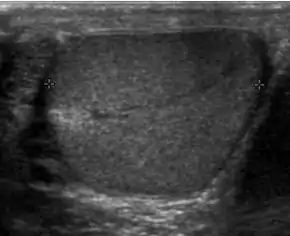

![]() Sonography of a normal testis. The normal testis presents as a structure having homogeneous, medium level, granular echotexture. The mediastinum testis appears as the

hyperechoic region located at the periphery of the testis as seen in this figure. | |

The normal adult testis is an ovoid structure measuring 3 cm in anterior-posterior dimension, 2–4 cm in width, and 3–5 cm in length. The weight of each testis normally ranges from 12.5 to 19 g. Both the sizes and weights of the testes normally decrease with age. At ultrasound, the normal testis has a homogeneous, medium-level, granular echotexture. The testicle is surrounded by a dense white fibrous capsule, the tunica albuginea, which is often not visualized in the absence of intrascrotal fluid. However, the tunica is often seen as an echogenic structure where it invaginates into the testis to form the mediastinum testis. In the testis, the seminiferous tubules converge to form the rete testes, which is located in the mediastinum testis. The rete testis connects to the epididymal head via the efferent ductules. The epididymis is located posterolateral to the testis and measures 6–7 cm in length. At sonography, the epididymis is normally iso- or slightly hyperechoic to the normal testis and its echo texture may be coarser. The head is the largest and most easily identified portion of the epididymis. It is located superolateral to the upper pole of the testicle and is often seen on paramedian views of the testis. The normal epididymal body and tail are smaller and more variable in position.